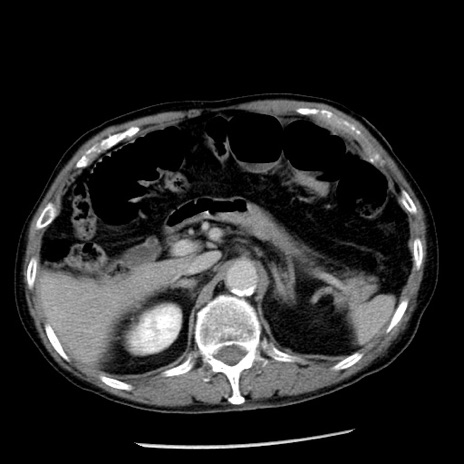

症例26(横断像)

【症例】80歳代男性

【主訴】嘔吐

【現病歴】昨晩2回嘔吐あり、今朝になっても嘔吐あり。来院。

【既往歴】胃潰瘍

【身体所見】意識清明、BT 37.6℃、BP 166/95mmHg、HR 100bpm、SpO2 97%、腹部:平坦・軟、腸蠕動音聴取良好、圧痛なし。

【データ】WBC 21900、CRP 1.46